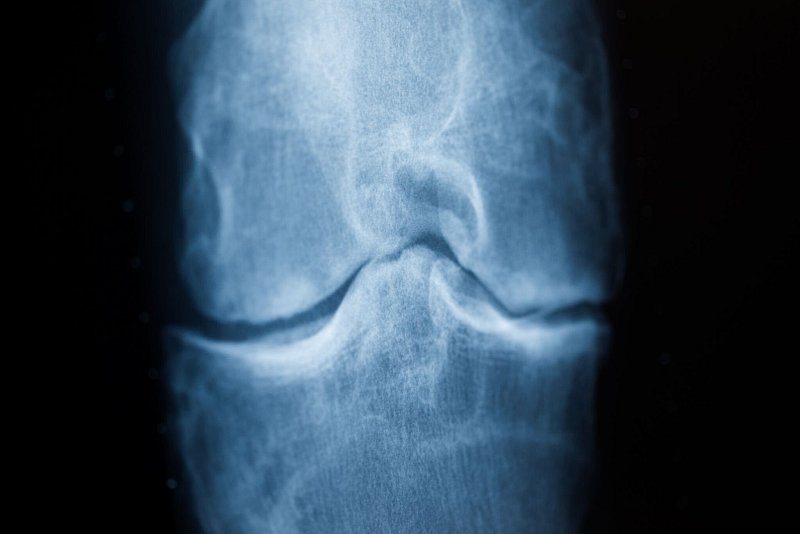

Das Team um Valentina Mazzoli mit Forschern des Klinikums Langone Health der New York University sowie der Universität von Utah und Stanford hat nun untersucht, ob konkret eine Veränderung der Fußposition beim Gehen die Belastung des Gelenks verringern kann.

Dafür wurden 34 Männer und Frauen mit leichter bis mittelschwerer Kniearthrose angeleitet, ihre Füße abweichend von ihrer natürlichen Ausrichtung um fünf oder zehn Grad verändert nach innen oder außen abzuwinkeln. Bei jedem Teilnehmer wurde geprüft, welche Fuß-Stellung zu ihm individuell passt. 34 weitere Betroffene erhielten unwissend eine Anleitung ohne Veränderungsvorschläge.

Sie alle sollten mindestens 20 Minuten täglich entsprechend laufen, schreiben die Wissenschaftler in der Fachzeitschrift «The Lancet Rheumatology». Über ein Jahr lang wurden Vergleiche gezogen, kontrolliert wurden die Auswirkungen des veränderten Gangs auf das Knie zum Ende mit MRT-Scans.